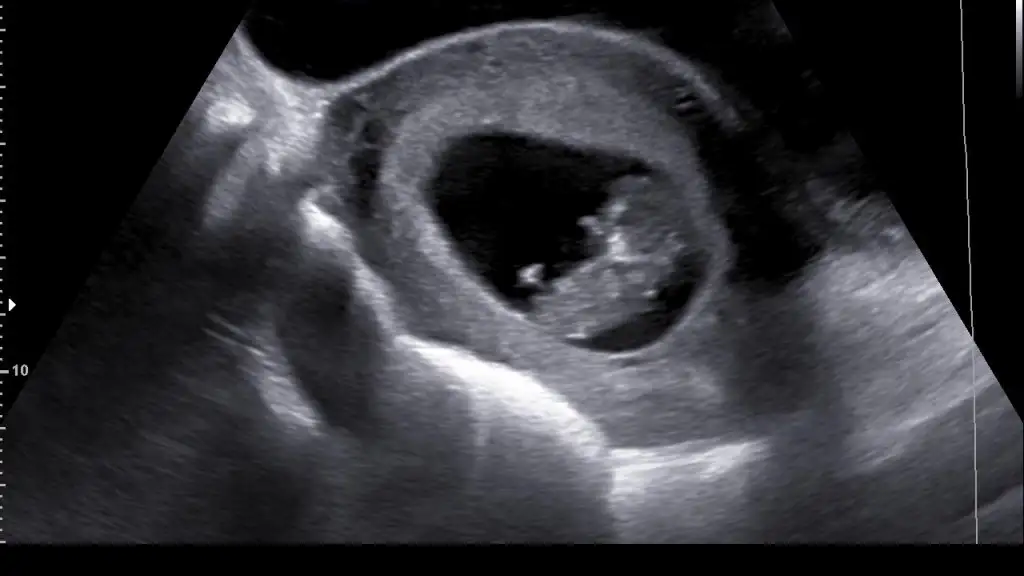

Cinsiyet tahmini yapabilecek olan var mııı? Birisi vardı kesin biliyor falan diyordu birileri. Bana kız gibi geldi ama doktor henüz bi şey demediii sizce???

Eklentiler

• D32E3B62-ACAA-4882-9DD1-2701FA0C9343.webp

D32E3B62-ACAA-4882-9DD1-2701FA0C9343.webp

17,7 KB · Görüntüleme: 87